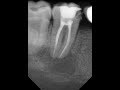

Пародонтоз — это серьезное заболевание, которое вызывает разрушение костной ткани, поддерживающей зубы. Важно знать, как возможно нарастить костную ткань при пародонтозе, чтобы сохранить здоровье и функциональность ротовой полости.

Одним из методов, применяемых для наращивания костной ткани при пародонтозе, является процедура регенерации. Она использует механизмы роста костей организма и способствует их восстановлению. Часто при регенерации применяются костные заменители и мембраны, которые помогают стимулировать рост новой кости.

Другим методом, который может быть применен для наращивания костной ткани, является аугментация. В ходе этой процедуры используются различные материалы, такие как собственная кость пациента, синтетические материалы или диагностированные растительные кости, чтобы укрепить и нарастить существующую костную ткань.